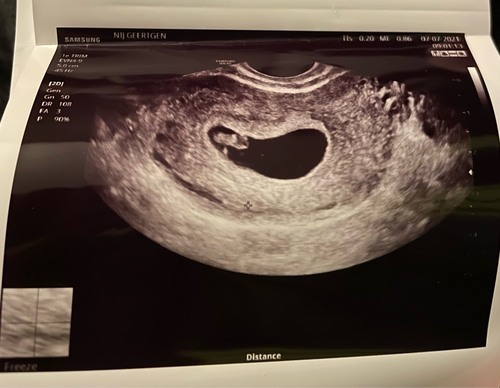

Hier met 6 weken naar Jan de koning geweest.

Alles was goed incl kloppend hartje 🥰❤️

Zaterdag gaan we weer ❤️